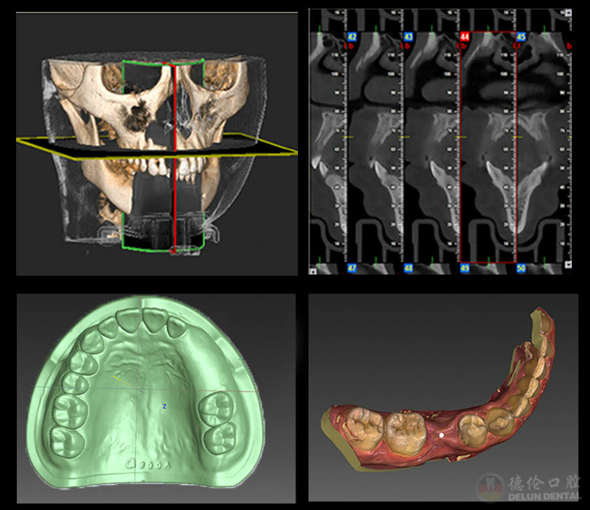

D3高配版数字化舒适种牙除了舒适麻醉诊疗的使用,得以实现的另一个不可缺少的技术是数字化种植技术,即获取缺牙者口内情况和数据(牙槽骨的高度/密度/宽度等)后,专家通过电脑反复设计和模拟其植体受力的均衡和植体植入的角度等问题,输出数字化导板辅助种植,无需翻瓣缝合即可完成种植,手术伤口只有米粒大小,术后当天就能正常进食,真正的微创舒适!

数字化种植技术输出数字化导板辅助种植,手术伤口只有米粒大小。